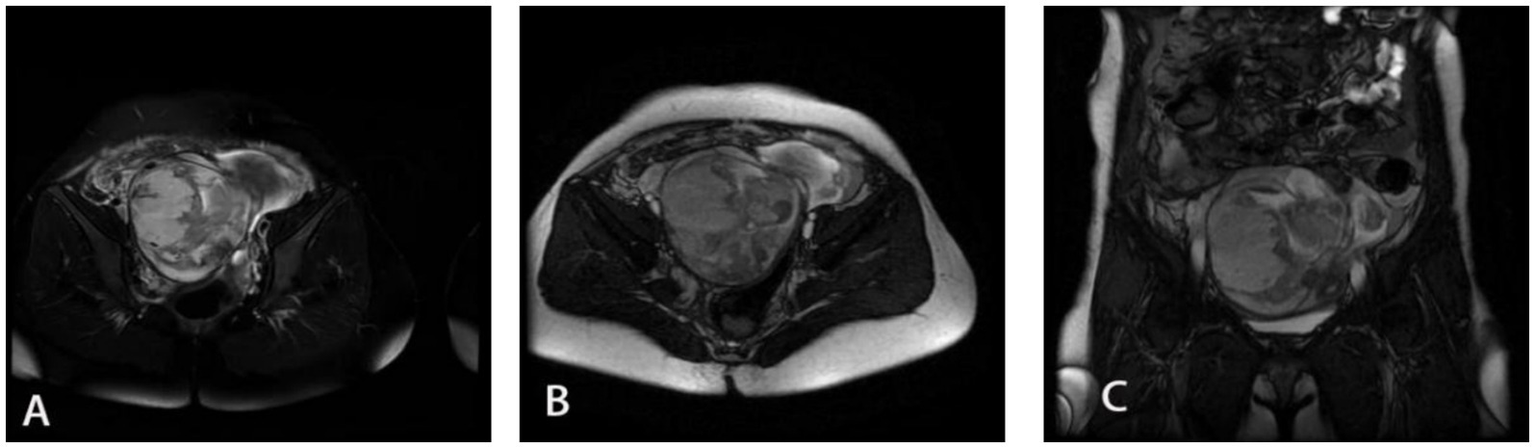

MRI images of Douglas pouch pregnancy of the fourth patient. The three pictures (A–C) show different sections of the lesion area of the fourth patient.

A 33-year-old female admitted with a 21 + 3-week history of amenorrhea, persistent abdominal distension for over half a month, and right lower abdominal heaviness for 4 days. Her symptoms began with unexplained abdominal distension and constipation accompanied by flatulence, which persisted for 6 days despite fluid replacement and laxative treatment at a local clinic. The right lower abdominal discomfort occurred without vaginal bleeding or discharge, prompting referral to our hospital. Ultrasound examination revealed no intrauterine fetal echo but detected a formed fetus with cardiac activity and movement in the abdominal cavity posterior to the right uterus. The patient had no prior pregnancy or trauma history before her last menstrual period 21 + 3 weeks earlier. Physical examination showed a blood pressure of 106/67 mmHg, pallor, lower abdominal fullness, and right lower abdominal tenderness, with the uterine fundus at umbilical level and the fetus displaced toward the right lower quadrant. Laboratory tests indicated severe anemia (hemoglobin 63 g/L) and elevated hCG (62,406.30 mIU/mL). MRI confirmed abdominal pregnancy with minimal uterine and pelvic effusion and a sacral canal cyst. Diagnosed with abdominal pregnancy and anemia, she received leukocyte-depleted red blood cell transfusion and underwent exploratory laparotomy. Intraoperative findings included 500 mL of non-coagulated blood and a duck egg-sized mass adherent to the uterine posterior wall and rectal fascia. The amniotic sac contained a 10 cm fetus, and the placenta was attached to the right broad ligament posterior leaf. Both ovaries appeared normal, though the fallopian tubes showed irregular thickening with fimbrial adhesions to the ipsilateral ovaries. The final diagnosis was Douglas pouch pregnancy. Postoperative hCG normalized by day 13, and the patient was discharged following an uncomplicated recovery.